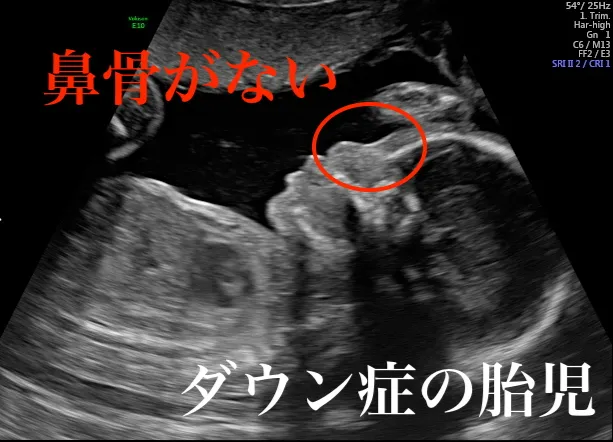

胎児の鼻骨が見えないか、形が小さいという超音波検査の結果は、染色体に異常があるかもしれないというサインです。

妊娠の初期段階で、胎児の鼻骨が確認できないことは、染色体異常の可能性を示す指標の一つです。超音波検査で胎児の顔の横から見た時、鼻骨は通常、鼻のすぐ下の皮膚よりも明るく映る線として見えます。この線が見えない、または皮膚よりも暗く見える場合は、鼻骨がないか、形成不全であると判断されます。

染色体の数が正常な胎児、13トリソミー、18トリソミー、21トリソミーを持つ胎児での鼻骨の欠損の割合は、それぞれ約2.5%、45%、53%、60%と報告されています。正常な染色体を持つ胎児で鼻骨が見えにくい場合、それは鼻骨が実際に欠けているのではなく、成長の遅れを示している可能性があります。胎児の頭殿長(CRL)が45~54mmの場合、約4.7%の胎児で鼻骨が見えにくく、CRLが74~84mmの胎児では約1%に減少し、胎児が成長するにつれてこの割合は徐々に減少します。

21トリソミー(ダウン症)の胎児では、妊娠初期よりも妊娠中期における鼻骨欠損の報告された感度は一般的に低くなります。中期においては、トリソミー21を持つ胎児の約30~40%で鼻骨が欠損しており、正常な胎児では欠損は約0.3~0.7%と非常に低いです。また、鼻骨の低形成は、トリソミー21の胎児の約50~60%、正常な胎児では6~7%で認められます。